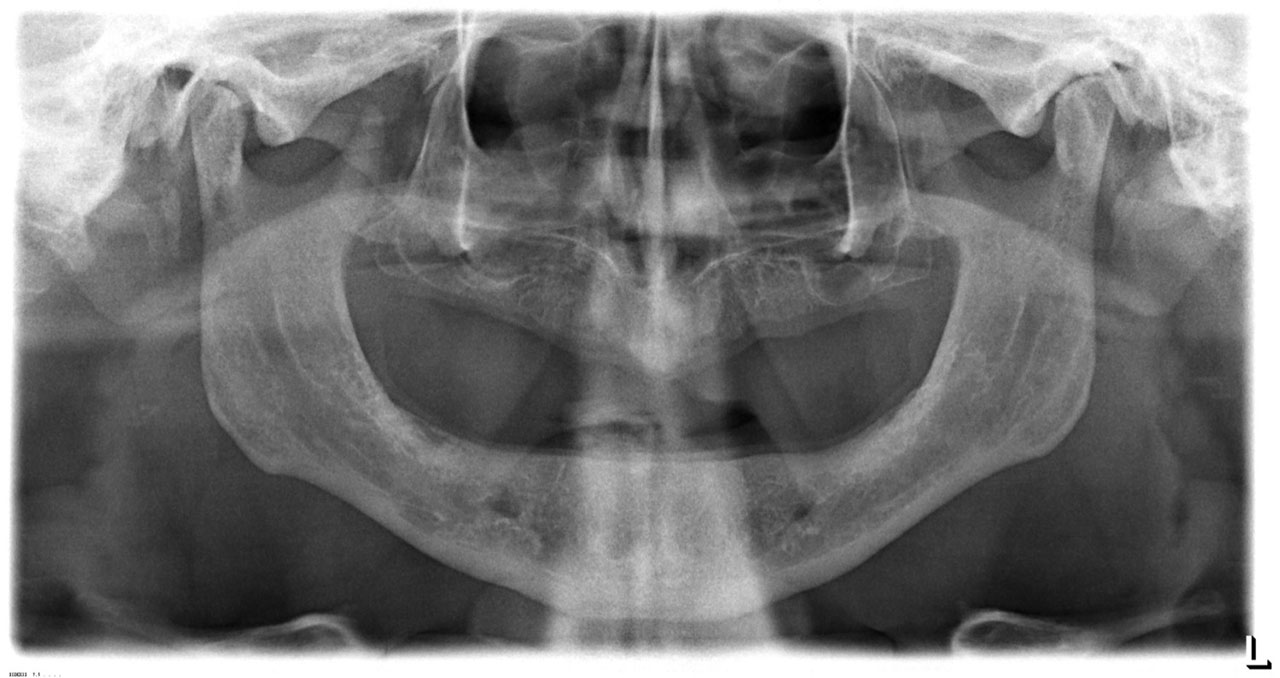

• esettanulmany-07

Teljes fogatlanság.

• esettanulmany-14

Alsó- felső fogatlan állcsont teljes implantációs helyreállítása.